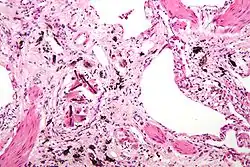

| Micrograph of asbestosis (with ferruginous bodies), a type of pneumoconiosis. H&E stain. | |